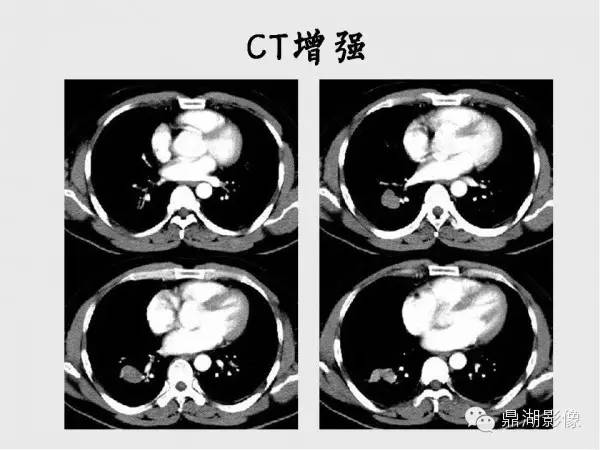

【病例】肺硬化性血管瘤1例CT影像表现与鉴别